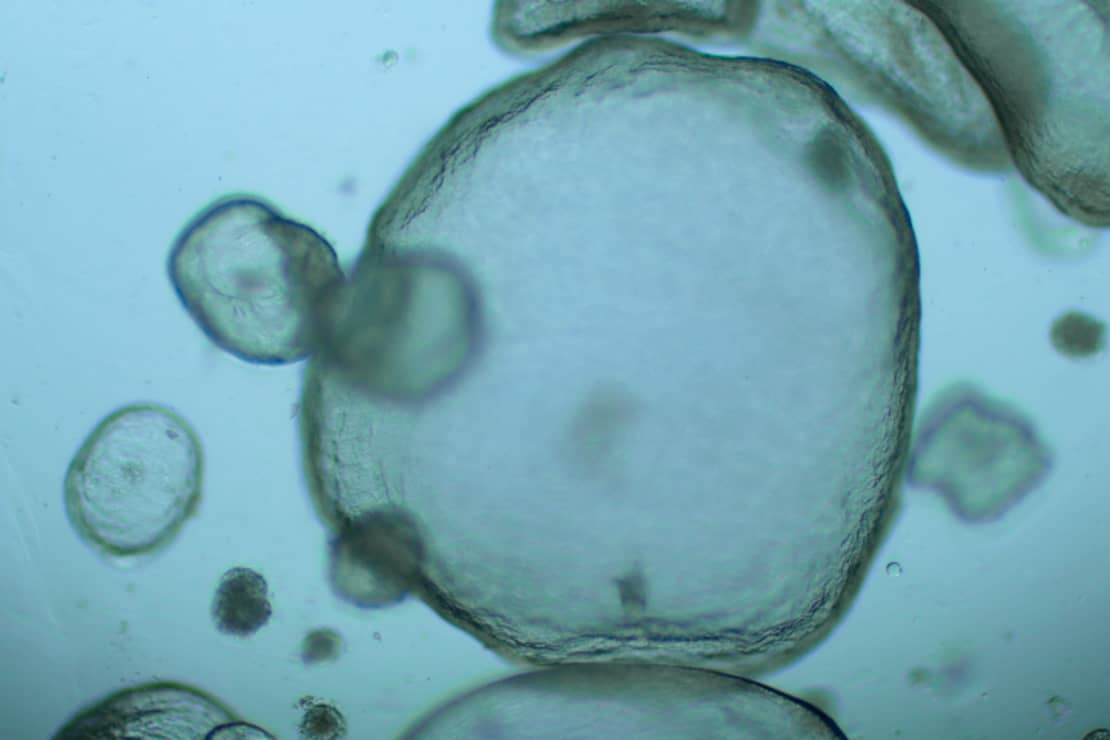

Développement et analyse de modèles organoïdes de trompes de Fallope humaines

Les chercheurs du laboratoire Développement embryonnaire, fertilité et environnement (DEFE) ont mis au point, en collaboration avec l’Institut de recherche en santé digestive (IRSD), des organoïdes humains de trompes de Fallope. Le modèle obtenu a montré un bon niveau de différentiation avec des cellules spécialisées.

Les chercheurs ont ensuite développé un système de coculture de ces organoïdes avec des spermatozoïdes humains conservés à la Germethèque afin d’étudier leur pouvoir fécondant. Ce système prometteur a permis de montrer que les spermatozoïdes conservaient leur mobilité pendant plusieurs jours, à des niveaux supérieurs à ceux obtenus au cours des opérations médicales d’assistance à la procréation. Il offre en outre la possibilité d’étudier en détail les interactions entre l’épithélium tubaire et les gamètes ou embryons, de mieux comprendre certaines infertilités et d’améliorer les techniques d’assistance médicale à la procréation.

Pour en savoir plus : Gatimel N. et al. (2025). Human fallopian tube organoids provide a favourable environment for sperm motility. Human Reproduction, 40(3):503-517.